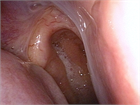

1. 診察、検査の要点を追記した。特に悪性腫瘍を見逃さないための下咽頭の診察方法について詳細に述べた。